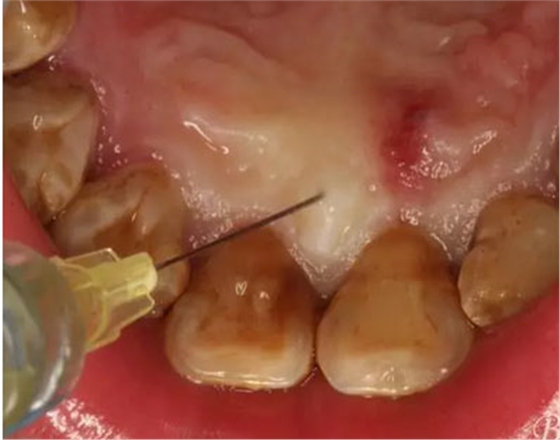

圖5.唇側(cè)局部無痛浸潤麻醉